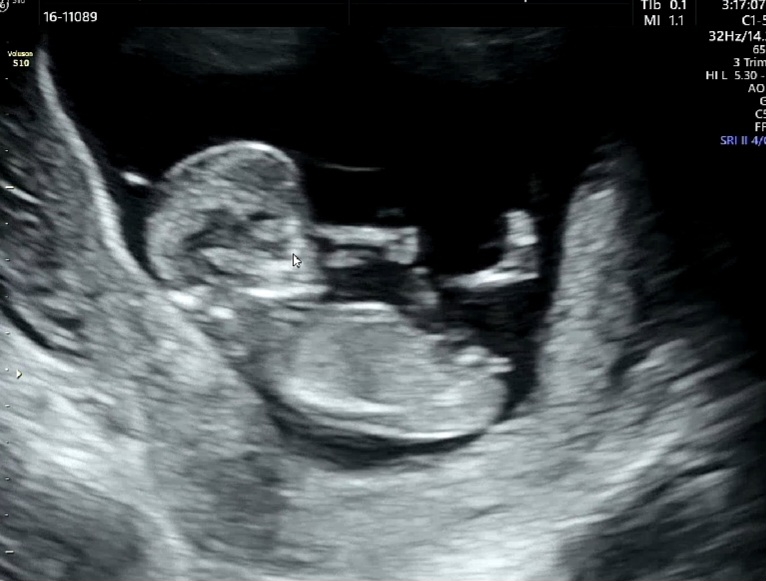

13주 성별각도법 아시는분 봐주세용🙇🏻♀️🙏🏻

둘찌 임신중입니당 혹시 각도법,성별 알수이쓰까용?😭

각도는 딸이용!